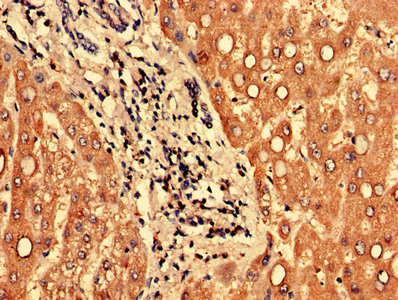

Immunohistochemistry of paraffin-embedded human liver tissue using CSB-PA769802LA01HU at dilution of 1:100